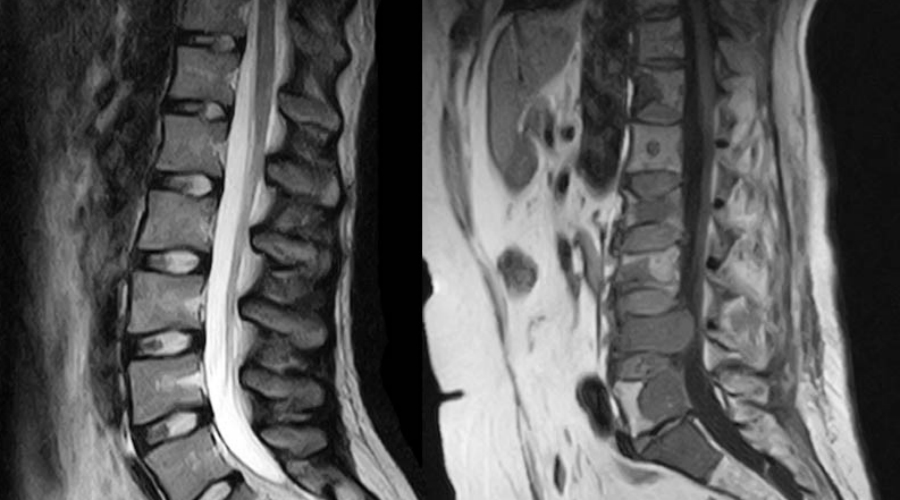

Телу приходится искать какую-то амортизацию при ходьбе. Довольно быстро развивается искривление позвоночника, лордоз, кифоз и сколиоз.

Под удар попадают и внутренние органы. Сдвинутые с места позвонки влияют на работу сердца, сдавленная диафрагма приводит к возникновению одышки. Страдает кишечник. Хуже всего, что искривление позвоночника может пережать нерв — грубо говоря, плоскостопие легко приводит к инвалидности даже молодого человека.

Проблемы с позвоночником

Влияние на внутренние органы